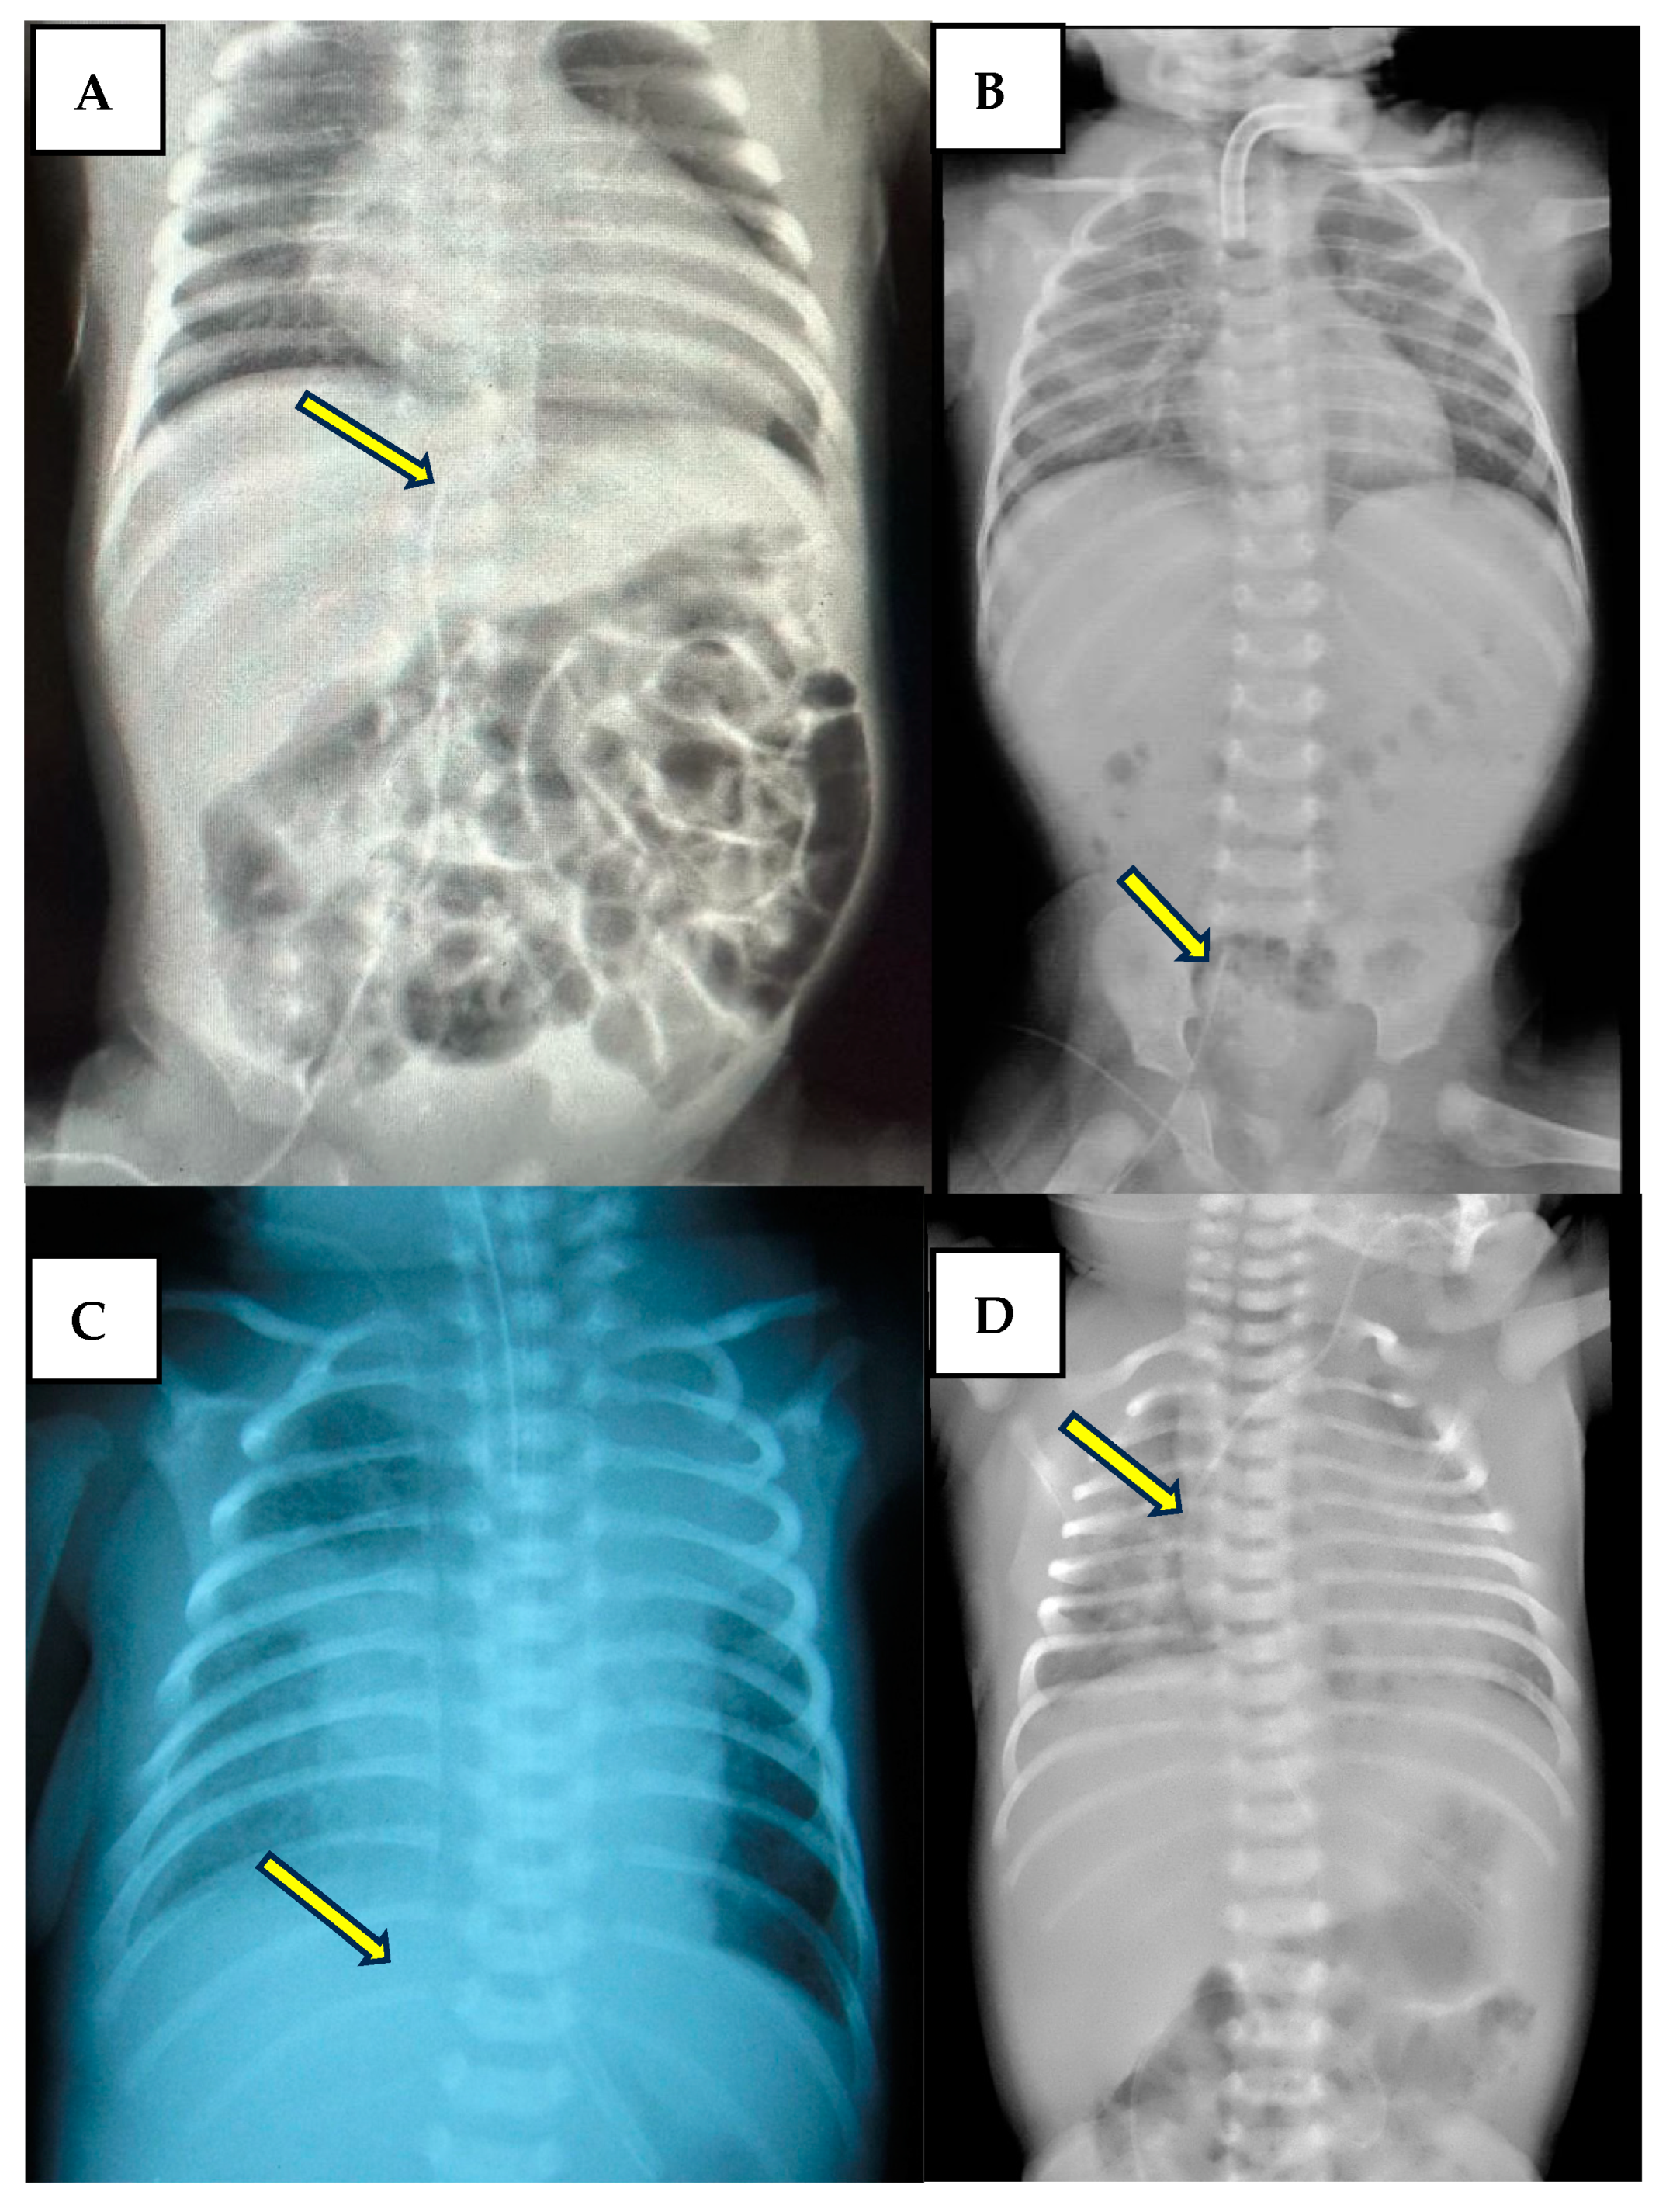

For the symptomatic cases, cardiac POCUS was essential for the rapid assessment of the cause and, when needed, for guiding the pericardiocentesis performed by our team of neonatologists. Variable echocardiography findings of neonatologist US examination are shown in Figure 4.

Figure 4. Pericardial effusion and tamponade. Picture (A) subcostal view-long axis-4 chambers view showing the CVC inside the right atrium (arrow). Picture (B) subcostal view-long axis-4 chambers view showing the diastolic collapse of the right ventricle (arrow).